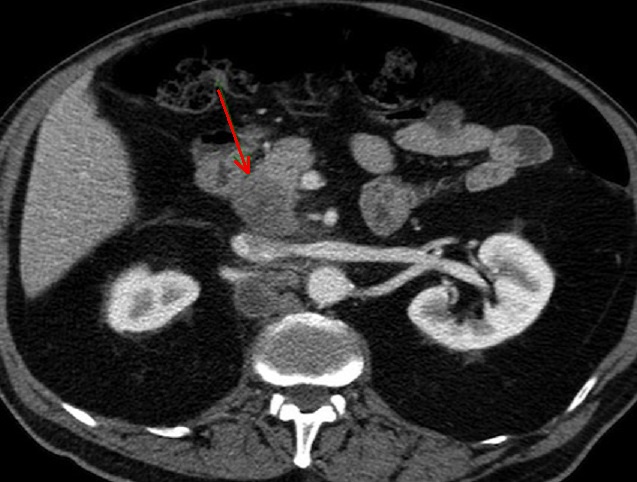

Image

radiologique TDM d'une lymphome pancreatique de la

tete du pancreas avec aspect lesionnel de forme

tumorale hypodense , homogene a mal limitee situe a

la tete du pancreas ( fleche rouge ) . Image TDM en

coupe axiale . |

|

Aspect lesionel TDM une masse a hypodense

, homogene mal limitee situe du corps pancreas(

fleche rouge . Rehaussement legere du tumeur apres

injection de contrast intraveineuse . Image

radiologique TDM plus contrast intraveineuse , coupe

axiale . |